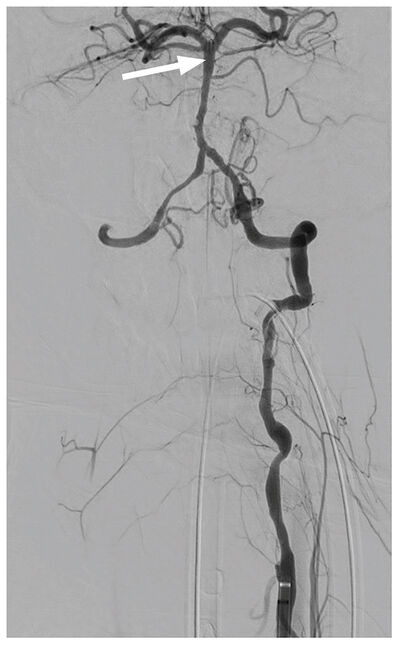

Tölvusneið (TS) mynd af heila sýndi stórt drep hægra megin í litla heila/hnykli (cerebellum) ( mynd 1 án skuggaefnis) og mikinn bjúg sem þrengdi aðeins að fjórða heilahólfi. TS-myndataka sýndi lokun í efsta hluta botnslagæðar á um 12-13 mm löngum kafla. Eðlileg fylling sást í aftari heilaslagæðum (PCA = Posterior Cerebral Artery) þar sem báðar aftari tengislagæðar (P. Com. = Posterior Communicating Artery) voru opnar ( mynd 2 ). Hryggslagæðin (VA = Vertebral Artery) var mjög óregluleg með afmarkaðar þrengingar og vaknaði því grunur um flysjun (dissection) í æðinni, sérstaklega vinstra megin, en sú æð var ríkjandi.

Mynd 2. TS æðamyndataka sýndi lokun í efsta hluta botnslagæðar (sjá hvíta ör) á um 12-13 mm löngum kafla þar sem báðar aftari tengislagæðar voru opnar. Hryggæðin var mjög óregluleg með afmarkaðar þrengingar og vaknaði því grunur um flysjun í æðinni, sérstaklega vinstra megin, en sú æð var ríkjandi.